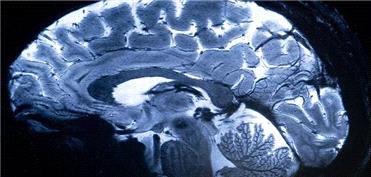

مدیتیشن فعالیت مغز را تغییر می‌دهد

سیاست و بازاریابی - ایسنا /نتایج یک مطالعه جدید نشان می‌دهد که مدیتیشن می‌تواند فعالیت مغز انسان را از نو شکل دهد. مدیتیشن یا مراقبه ممکن است ذهن را آرام کند، اما یک مطالعه اخیر ...